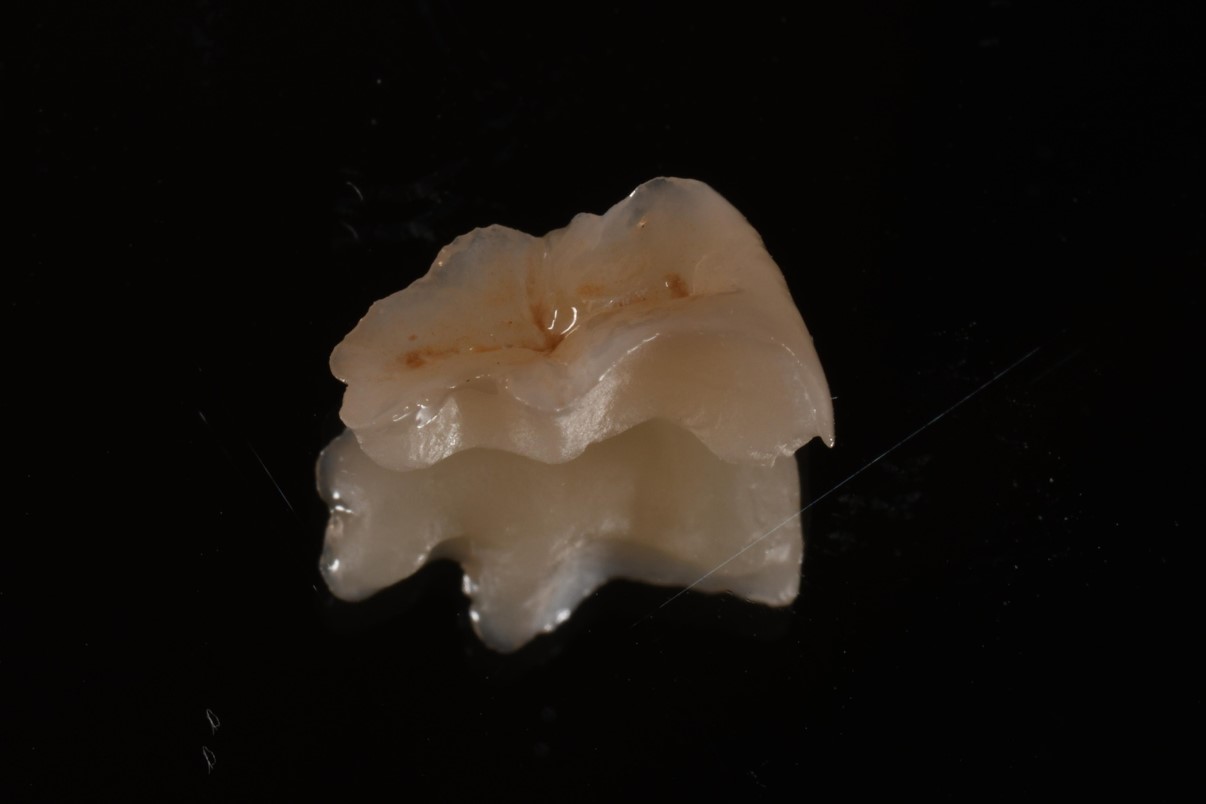

全瓷崁體